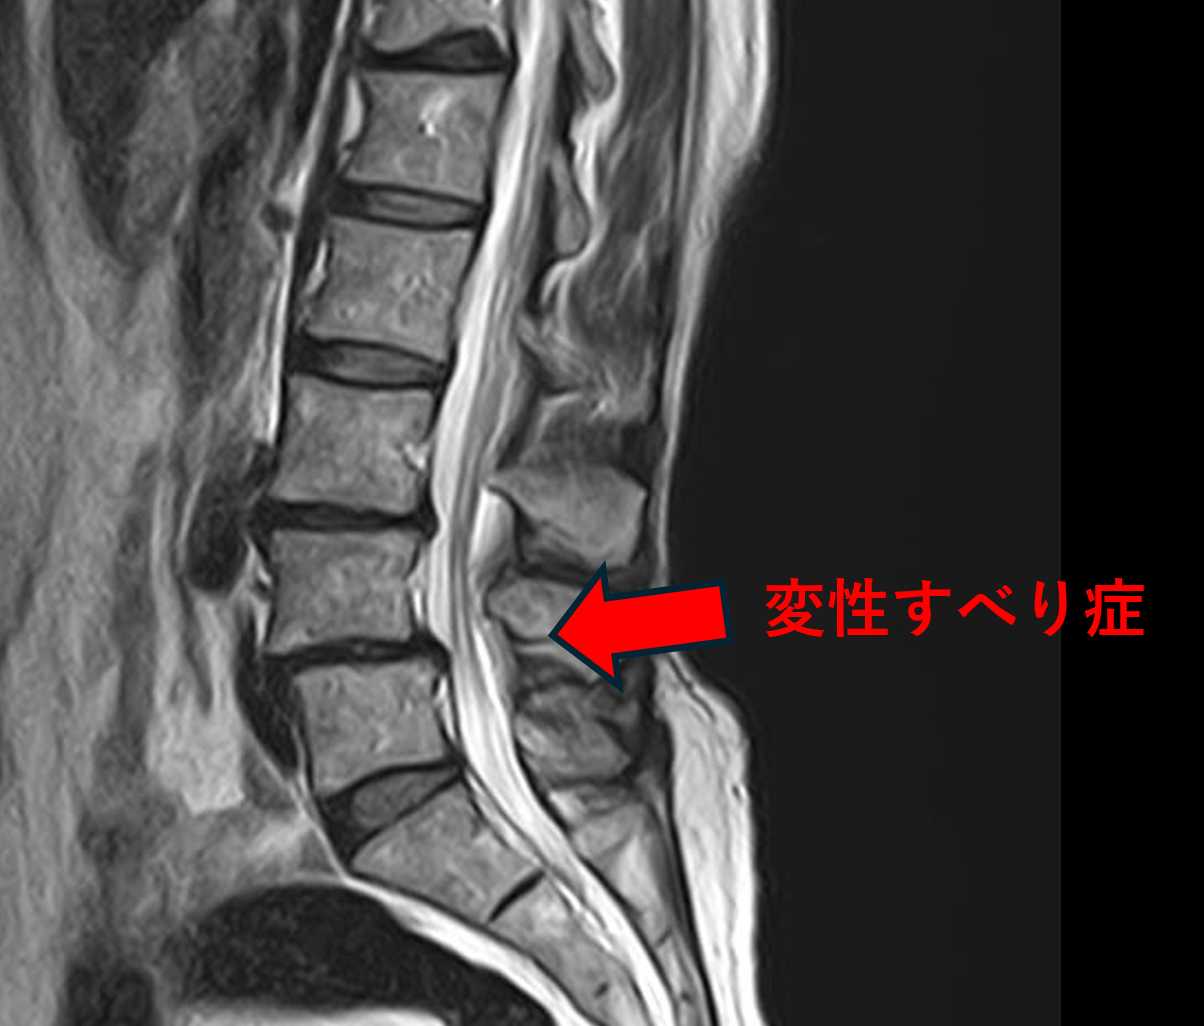

画像及び所見について

- L3/4 – 椎間板変性、膨隆

- L4/5 – 椎間板変性、膨隆、変性すべり

- L5/s – 椎間板ヘルニア

以上のことが画像上認められました。

L3/4、4/5、5/sの椎間板所見による脊柱管の圧排が、症状の原因の可能性が高い。